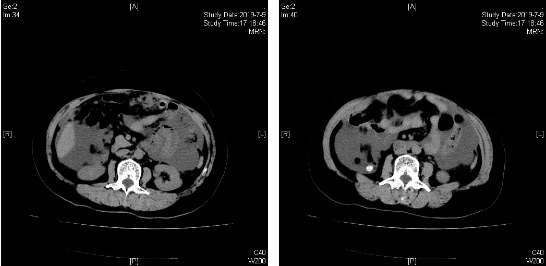

治疗前(2019.07.09)

治疗后(2020.05.27)